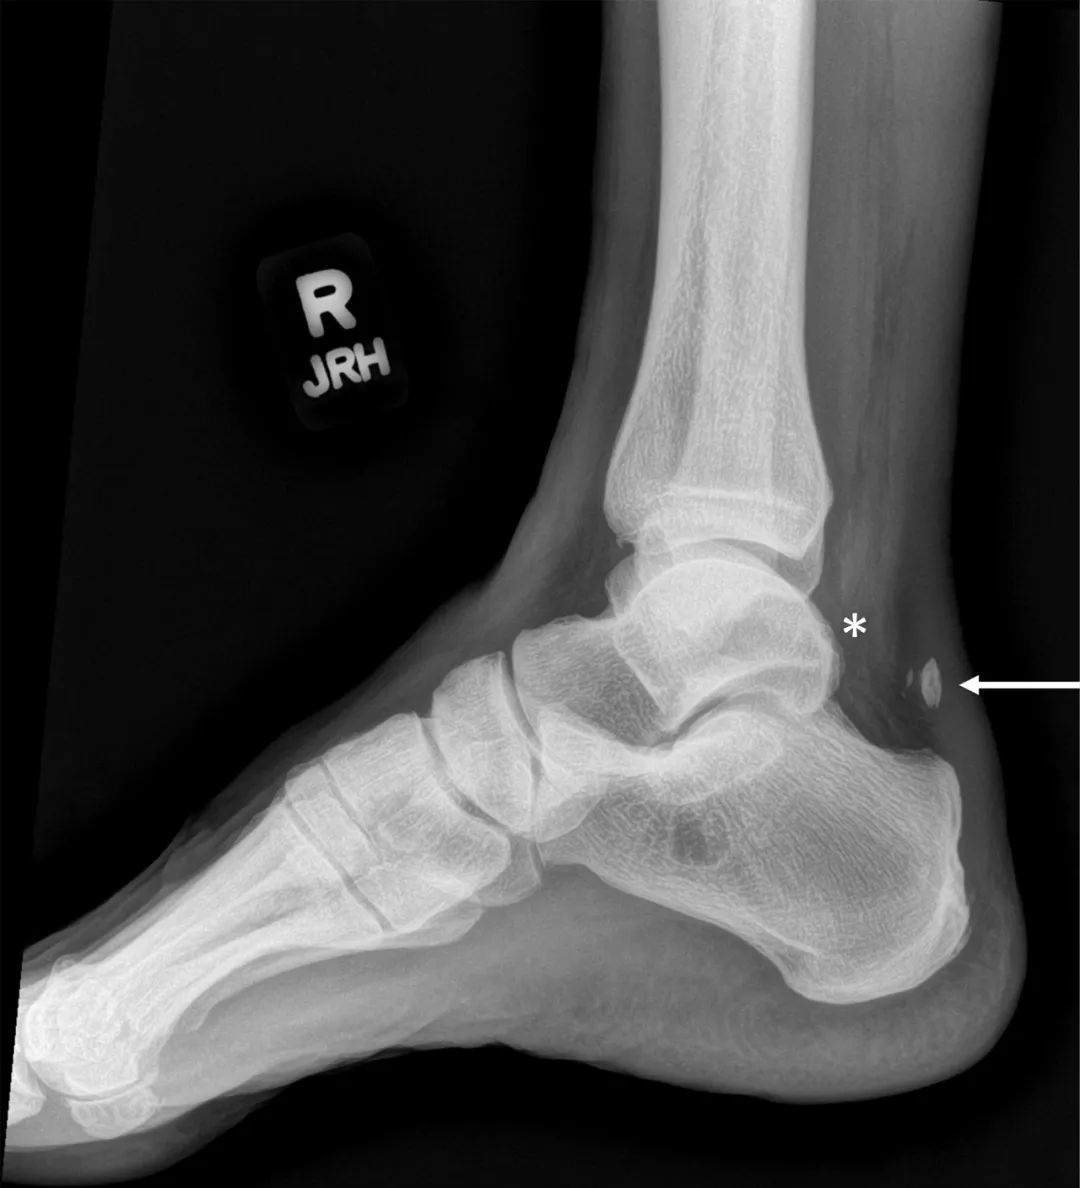

4. 影像

X 射线扫描可显示小腿、脚踝或膝部的多种类型的异常(尤其是骨骼和关节问题)。

跟腱撕裂。右踝关节侧位X线片显示跟骨附着物撕脱(箭头),表明退行性跟腱撕裂;Kager脂肪垫内异常密度(*),表明相关的跟骨后滑囊炎。MRI帮助确认跟腱撕裂,有2厘米的间隙。手术修复时证实肌腱完全断裂。这个病例说明了使用Kager脂肪垫对踝关节疾病的影像学诊断的重要性。

超声波(超声图)或磁共振成像(MRI)可用于评估小腿肌腱损伤和撕裂。